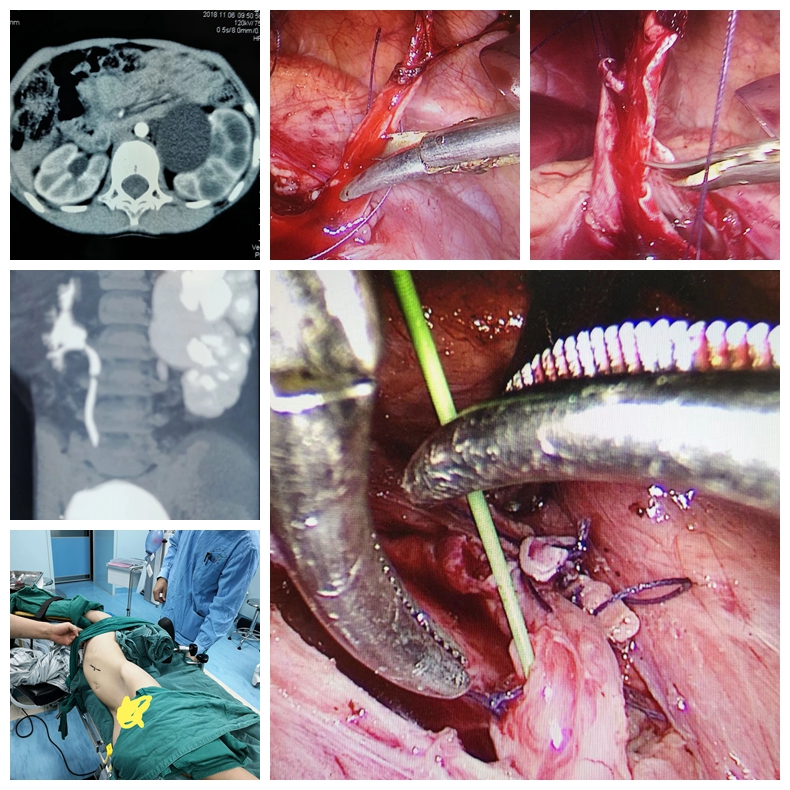

科室积致力于泌尿外科微创技术的创新和优化。在广泛开展腹腔镜肾癌根治术、肾部分切除术、前列腺癌根治术、全膀胱切除术及肾上腺肿瘤切除术等基础上,进一步扩大腹腔镜技术的覆盖范围,开展腹腔镜下腹膜后和盆腔扩大淋巴结清扫术等高难度手术。推动外科微创化与加速康复外科(ERAS)的紧密结合,打造成特色、优势技术,受到广大患者认可。泌尿系统结石疾病的诊治是我科的传统优势项目,保持着省内先进水平。我科应用经皮肾镜技术开展了一些高难度的肾结石手术,如严重脊柱畸形患者的肾结石、孤立肾肾结石、无肾积水的肾结石、马蹄肾肾结石等,而且手术均取得成功。泌尿系肿瘤的发病率逐年升高,其防治任重而道远。我科积极开展复杂性泌尿系肿瘤的诊治,尤其是巨大肾上腺肿瘤、巨大肾肿瘤、孤立肾较大肾癌的保留肾脏手术等。同时积极开展泌尿系肿瘤的防治研究,重点进行泌尿系肿瘤病因学的研究,尤其是寻找膀胱癌、肾癌和前列腺癌相关功能基因,从基因学角度寻找肿瘤特异标记物,提高泌尿系肿瘤早期诊断水平,并为进一步基因治疗提供基础。前列腺增生作为老年男性常见疾病一直以来是我们重点研究的方向和医疗特色之一。随着外科技术的不断进步及新的医疗设备的不断涌现和完善,TURP的金标准地位逐渐受到挑战,如经尿道钬激光前列腺剜除术技术日臻完善,大有取代TURP之势。目前我科已积极开展经尿道钬激光在良性前列腺增生治疗中的应用,取得了良好的治疗效果。我科针对目前男性疾病诊治需求量迅速增加的现状,积极开展男科的特色诊疗,范围包括男子勃起功能障碍、早泄、男性不育症、精索静脉曲张、血精、阴茎硬结症、睾丸附睾疾病、男子生殖系统内分泌疾病等。开科以来典型手术介绍如下:

腹腔镜下右肾癌根治性切除+腹膜后淋巴结清扫术治疗肾癌合并腹膜后淋巴结转移的病例

开放性左肾癌根治性切除+静脉癌栓取出+腹膜后淋巴结清扫术治疗左肾癌合并静脉癌栓、

腹膜后淋巴结转移的病例

腹腔镜下离断式肾盂输尿管成型术治疗小儿肾盂输尿管交接部狭窄的病例

腹腔镜左肾上腺切除术治疗大体积嗜铬细胞瘤的病例

超定位下经皮镜碎石取石术治疗右肾铸型结石的病例